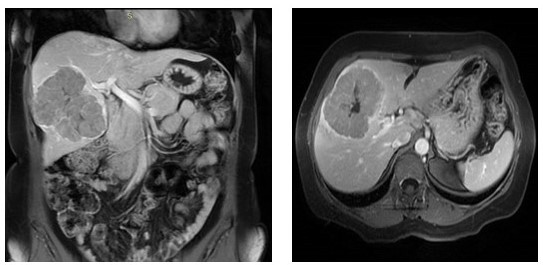

RESONANCIA MAGNÉTICA ABDOMINAL 11/04/2023

Lesión sólida heterogénea de márgenes bilobulados parcialmente circunscrito en segmento V y VIII, con realce pos-contraste en fase arterial que se mantiene estable en fases tardías y área hipodensa central hipocaptante que puede corresponder a fibrosis, mide 8 cm x 6 cm (Figura 1 y 2). Volumen hepático total de 1200 cm3 (Lóbulo derecho 900 cm3 y lóbulo izquierdo 300 cm3 y la lesión derecha con volumen de 380 cm3 (30 % del volumen aproximadamente del total del parénquima hepático).